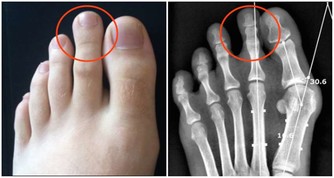

我的喉嚨偶爾會跑出米粒大小,黃白色的不明顆粒,

不會痛也不會不舒服,

但就是很臭,

這個症狀少說也有十幾年了,

才發現原來這是扁桃腺結石,

他耐心的用畫圖方式告訴我結石藏在扁桃腺的隱窩,不易清除,

所以通常會以開刀切除扁桃腺來解決,

另 外,蔡立泰醫師也表示,扁桃腺結石通常看起來像白色或微黃色的小石頭,有時候吐出來時,可以把這些小石頭壓碎,並出現臭臭的味道。扁桃腺結石目前 大多認為是由食物的殘渣及壞菌卡在扁桃腺表面的隱窩中所形成。有些人會感覺到喉嚨卡卡的感覺,嚴重的患者更可能出現頭痛、咽喉疼痛、吞嚥困難、耳朵痛癢、 甚至嘔吐等情形。也因為這些細菌和食物的殘渣以及部分壞死組織的鈣化,所以可能在講話時散發出一些腐爛的臭味,也就是我們所謂的口臭。